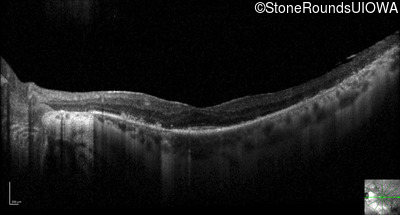

Optical Coherence Tomography - Left - 20/25 sc

Exemplar / OCT Stack

OCT Stack